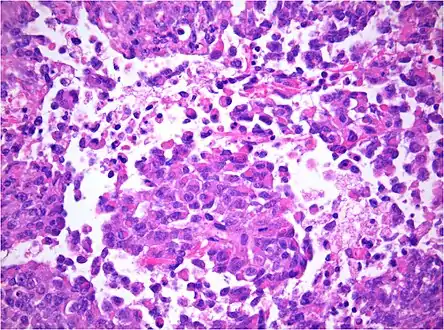

AT/RT and rhabdoid tumor share the term "rhabdoid" because under a microscope, both tumors resemble rhabdomyosarcoma.

The tumor histopathology is jumbled small and large cells. The tissue of this tumor contains many different types of cells including the rhabdoid cells, large spindled cells, epithelial and mesenchymal cells, and areas resembling primitive neuroectodermal tumor (PNET). As much as 70% of the tumor may be made up of PNET-like cells. Ultrastructure characteristic whorls of intermediate filaments are seen in the rhabdoid tumors (as with rhabdoid tumors in any area of the body). Ho and associates found sickle-shaped embracing cells, previously unreported, in all of 11 cases of AT/RT.[18]